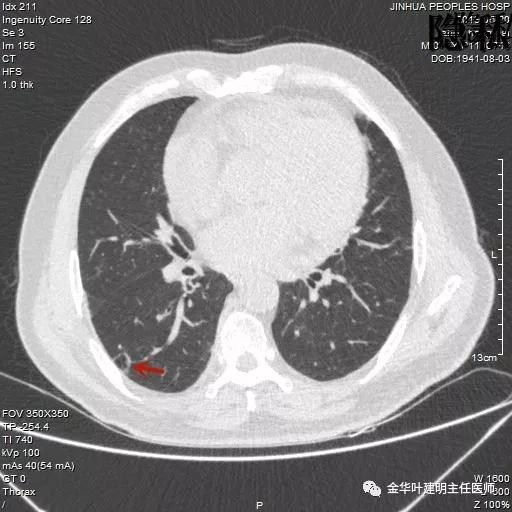

如果我们把各个时候的片子放在一起对比,就会发现右下叶背段的空腔性病灶是从无到有,并逐渐进展的:

逐渐进展的空腔性病灶,特别边缘还是磨玻璃样的,需要特别当心,虽然有的层面看上去似肺大泡,但仍需我们提高警惕,注意必要的随访复查。

考虑恶性,那么就得考虑住院并行手术治疗,入院后再进一步查靶扫描,结果如下:

是不是囊腔型腺癌?周围病灶,有空腔,有磨玻璃成份,当然要考虑,但我觉得因为似乎是以往是空腔性病变,今年其内部分填充了实性成分,要考虑粘液腺癌可能为大。当然反正都得手术切除治疗。